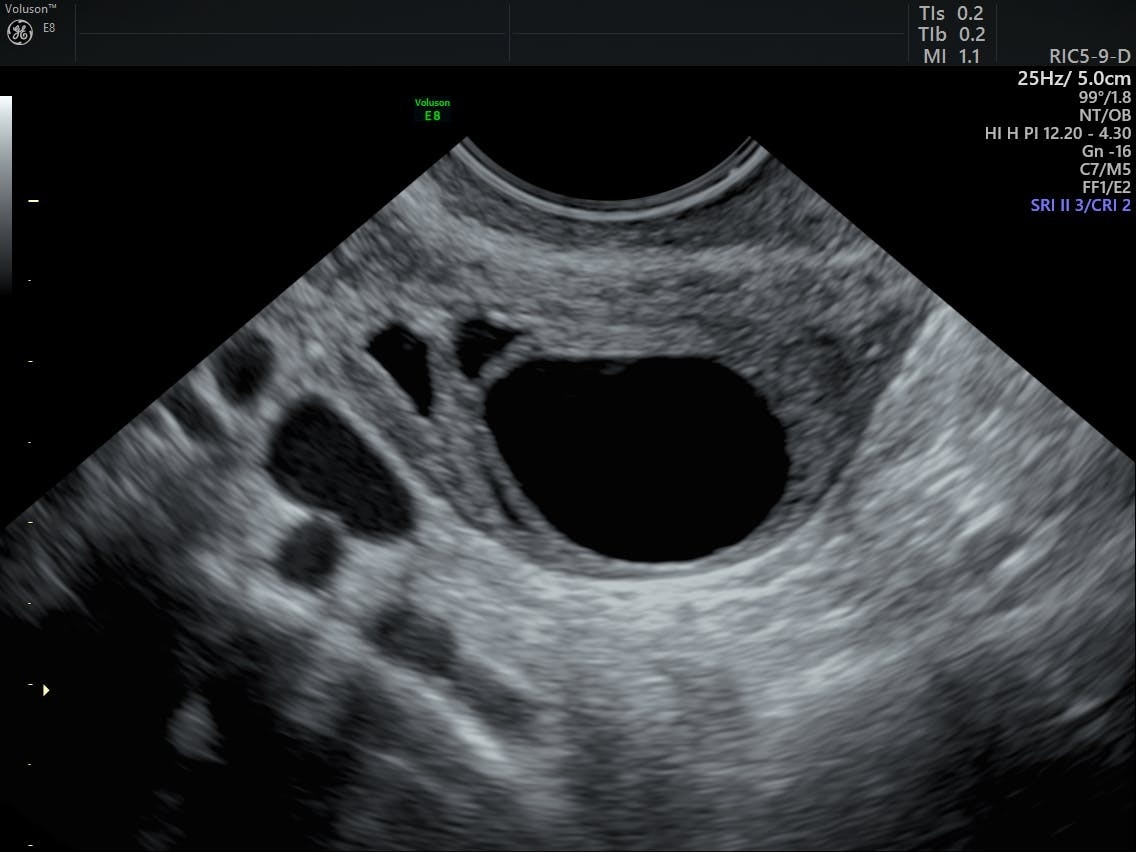

Диагностика кисты

• УЗИ-картина. Доброкачественные опухоли имеют ровные, гладкие контуры, однородное содержимое, могут быть функциональными. Злокачественные чаще имеют перегородки, неоднородную структуру, включения, усиленное кровоснабжение.